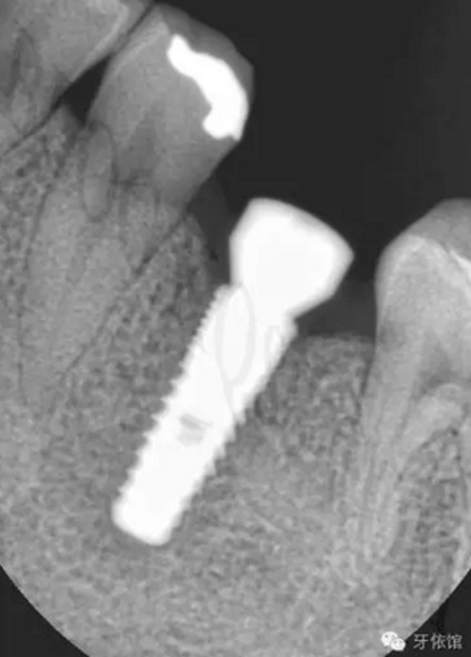

再將烤瓷冠就位,拍X光片,檢查烤瓷牙與基臺之間是否密貼。

但是由于微創(chuàng)種植一般都不切開翻瓣,出血少,疼痛輕,無腫脹,患者較容易接受。所以如果條件允許,您不妨可以 找一個簡單的病例試一試。在手術(shù)之前,必須要對病例進行詳細(xì)的分析,周密的計劃。如果我們術(shù)前對種植區(qū)域牙槽骨沒有進行充分的分析就盲目的操作,就可能會出現(xiàn)一側(cè)牙槽骨剩余量不足1mm的情況,導(dǎo)致種植后種植體脫落,或一側(cè)植體達骨面以下,而另一側(cè)卻有螺紋暴露。

如下圖所示從外觀上來看,擴孔的位置位于牙槽嵴頂?shù)闹醒氩课?,但是頰舌側(cè)粘膜及粘膜下組織厚度不一,會造成我們判斷有誤。